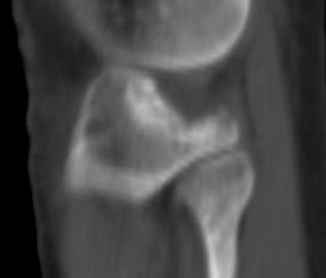

Здравствуйте, уважаемые коллеги!Подскажите, пожалуйста, какой выбрать доступ и способ фиксации при импрессионном переломе заднего отдела наружного мыщелка большеберцовой кости. Женщина 40 лет, травму получила 02.01.2008, катаясь на горных лыжах.Есть ли здесь необходимость использовать задний доступ, или можно справиться через наружный? Есть ли шансы сделать закрыто - под ЭОП через медиальное "окошко" поднять забойником суставную поврехность? Какой лучше использовать фиксатор?Спасибо.

Медиально, обычно на протовоположной

строне, делается окно в кортикальном слое, кривым забойником под рентгеном поднимается импрессия.

Это техника применяется, когда имеется

центральная импрессия, а при ипрессии с краевым переломом - после приподнимания импрессии опорная (Butress) пластина, как на снимке.

In this situation, where the fragment is posterolateral, one needs a posterior approach, either as described by Timothy Bhatacharya et al in 2005 in JOT, which involves taking down the medial head of the gastrocnemius, or the Lobenhoffer paper which involves a transfibular approach.